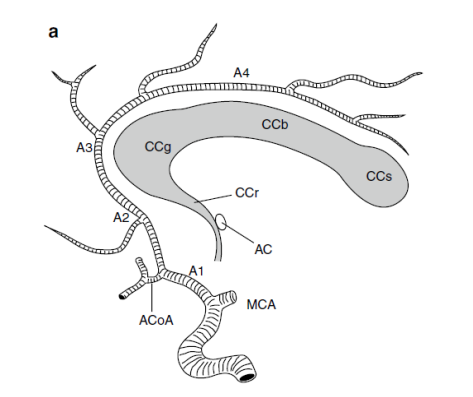

Intracranial vessels

Middle

cerebral artery

(From Neurovascular imaging –

2011)